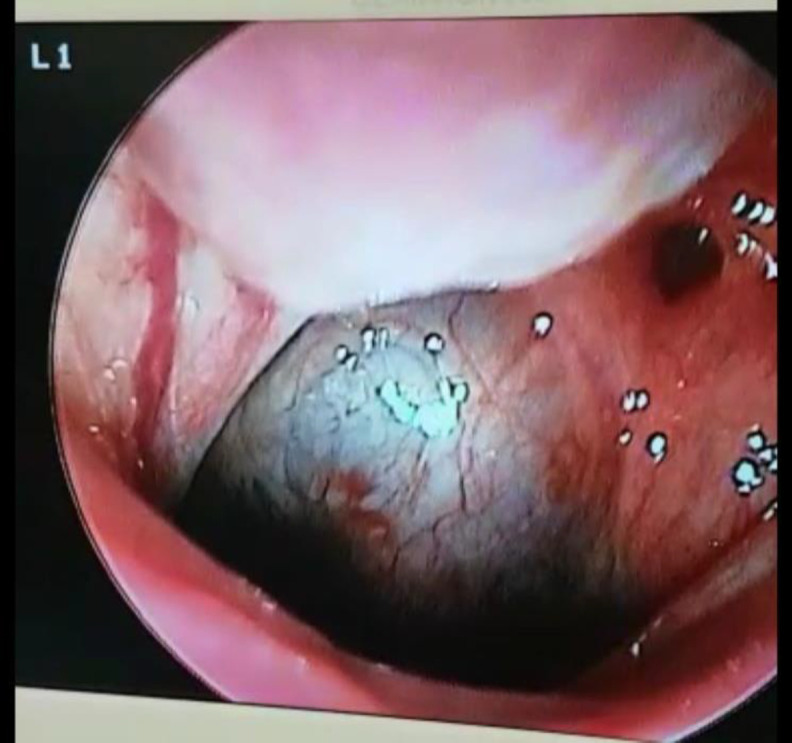

简介大多数鼻咽囊肿无症状且罕见。然而,这些病变很少在常规内窥镜检查和造影检查中被发现。上鼻咽 Thornwaldt 囊肿是一种先天性粘膜良性囊肿。甚至更少见的是,它们会引起不明原因的鼻窦症状,如鼻出血、视力问题和鼻腔堵塞:病例报告:我们在此报告了一例冠状病毒感染后新发听力损失的病例,其影像学检查显示鼻咽部肿块:结论:感染冠状病毒-19 后,我们应考虑高危患者的腮腺囊肿和 Thornwaldt 囊肿。结论:感染科维-19 病毒后,我们应考虑高危患者的腮腺囊肿和 Thornwaldt 囊肿,另一方面,科维-19 病毒感染后的渐进性听力损失也可能是这类囊肿激活所致。

Case report: Here, we report a case with new-onset hearing loss after the coronavirus infection, in which his imaging investigation showed a nasopharyngeal mass.